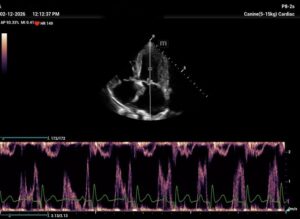

I see MS at all ages, because it is frequently missed in young dogs. But this case is not a MS. It is diagnosed as a combination of 2D-echo findings and the typical Minflow profile (E-wave very high frequently >2 m/s) confluent with A-wave. See image and video.

and video